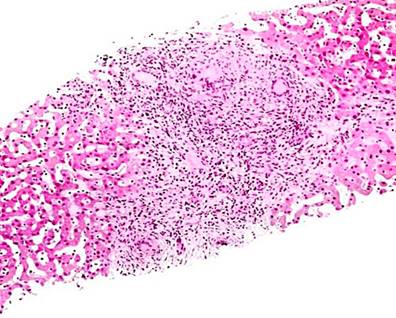

Se enviaron tres fragmentos de color pardo grisáceo, consistencia elástica, con nódulos blanquecinos, de los cuales el mayor mide 1,6 x 1 x 0,5 cm y el menor 0,8 x 0,3 cm. El espécimen fue procesado en su totalidad y se realizaron tinciones histoquímicas (reticulina, ácido peryódico de Schiff [PAS] y tricrómico de Masson) para la evaluación microscópica.

En la evaluación microscópica se observó tejido hepático con alteraciones de la arquitectura normal por la presencia de un área extensiva de necrosis de caseificación. En el exterior se apreciaron células epitelioides, células gigantes de tipo Langerhans y fibrosis. Además, se encontró un remanente de hepatocitos con arquitectura distorsionada con espacios porta que presentaban expansión fibrosa, degeneración hidrópica y congestión sinusoidal. En algunas áreas se observó proliferación ductal. La conclusión de la biopsia hepática indicó un proceso inflamatorio granulomatoso con necrosis de caseificación, compatible con M. tuberculosis. La Figura 5 muestra una representación de lo observado en el corte histológico. Ante estos hallazgos, el departamento de patología sugirió correlacionar los hallazgos histopatológicos con la clínica de la paciente.

Figura 5 Corte histológico de tejido hepático con granuloma con células gigantes. Fuente: Themes U. Mycobacterium tuberculosis11.